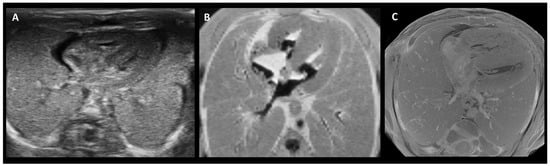

Figure 2.

Side-by-side comparison of PMUS (A), 9.4 T MRI (B), and micro-CT (C) images showing a cross-section of the thorax of a 15-week-old fetus, following termination of pregnancy. While all three show the general composition of the thorax, micro-CT generated a more detailed image of the structural anatomy. Adapted from [74].

An overview was created of the cost, resolution, scanning time, and the ability to scan despite maceration for the three above-mentioned imaging techniques (Table 4). PMUS offers a relatively simple, accessible, and inexpensive way to scan fetuses. However, the resolution of the images is low and the technique is difficult to apply in miscarriages due to the small size and possible maceration of the fetus [77,79,80,82]. Both UHF-MRI and micro-CT produce relatively high-resolution images, but the resolution of micro-CT is significantly higher and the technique is less time-consuming and estimated to be more cost-effective than UHF-MRI [60,62,67,68,69,74,78,81] (Figure 2). As fetal size increases, micro-CT and UHF-MRI become less effective because of constraints such as the small bore size of UHF-MRI and the longer staining time required for micro-CT. Therefore, for fetuses beyond 20 weeks of gestation, low-field MRI is considered more appropriate (Figure 3) [67].